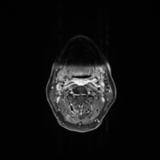

Acute calcific deposit on the enthesis of the longus colli muscle

The severe cervical spine pain prompted an emergency MRI examination, which showed a clear prevertebral inflammatory soft tissue process. On close inspection, a calcific deposit anterior to the dens axis can already be suspected on MRI (especially T2 or axial T1fs Gd+). The calcium depot is only shown very fluffy on X-ray and CT, suggesting an acute stage with precipitation/resorption of the calcific milk.

Therapy is initially conservative. Punctures and surgery of the calcific deposit can be done from endooral.

The longus colli muscle is a less common location of this condition, which should be referred to as HADD or acute calcific deposit. Also affected may be supraspinatus tendon and other tendons of the rotator cuff, extensor carpi radialis tendon, deltoid muscle, or hip adductors.